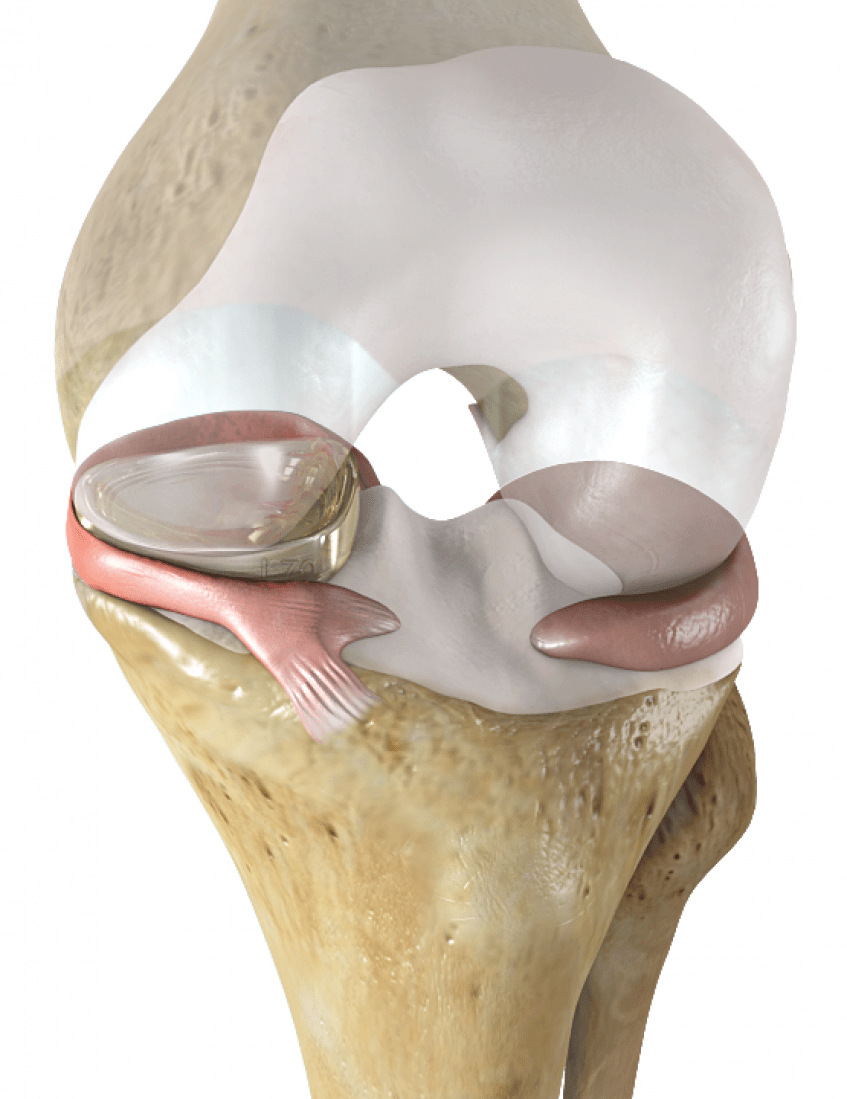

Анатомические изображения менисков и коленного сустава

Раздел: Иллюстрированные советы